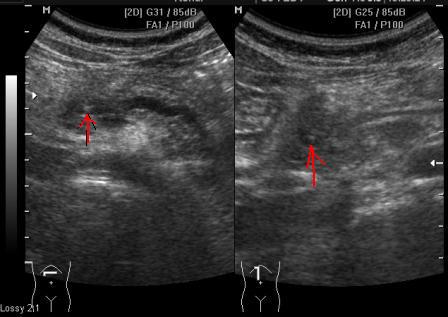

На момент осмотра пациентку ничего не беспокоит. В моче диастаза 3300.

Размеры поджелудочной:16мм -11мм-17мм

Можно и нужно указать и то и другое.

Хронический калькулезный панкреатит, вирсунголитиаз.

Сегодня девочка пришла на плановое УЗИ: